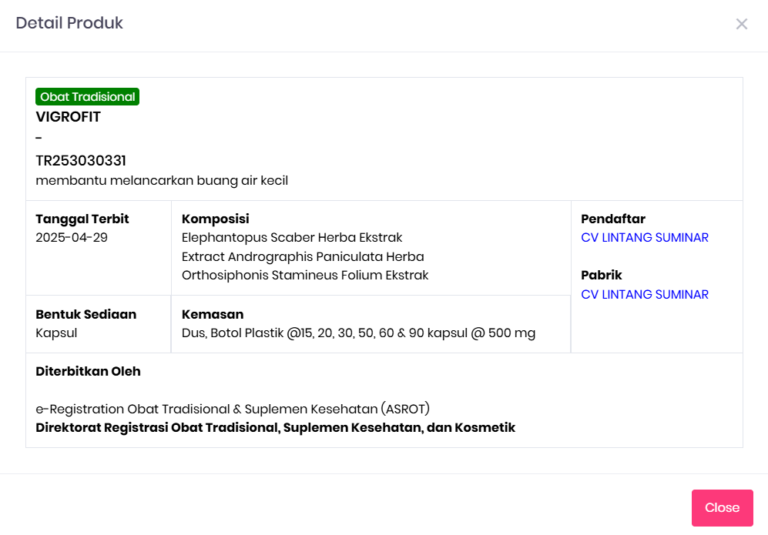

Apa Itu Vigrofit?

Obat Herbal Kencing Nanah (Obat Gonore) – Vigrofit merupakan obat herbal alami ampuh untuk redakan gejala penyakit kencing nanah, gonore, sifilis dan Raja Singa pada pria dan wanita.

Mengapa Harus Pilih Obat Kencing Nanah Vigrofit?

Obat Alami Kencing Nanah (obat gonore) – Vigrofit adalah solusi herbal alami yang membantu meredakan keluhan gonore secara aman tanpa prosedur medis mahal dan tanpa efek samping. Banyak orang yang menunda pengobatan akhirnya memerlukan waktu dan biaya lebih besar karena infeksi menyebar.

Dengan formula herbal berkonsentrasi tinggi, Vigrofit terbukti mampu meredakan gejala gonore dalam 3 hari, membantu mengembalikan kenyamanan dan kesehatan secara alami.

Vigrofit Aman Terverifikasi BPOM